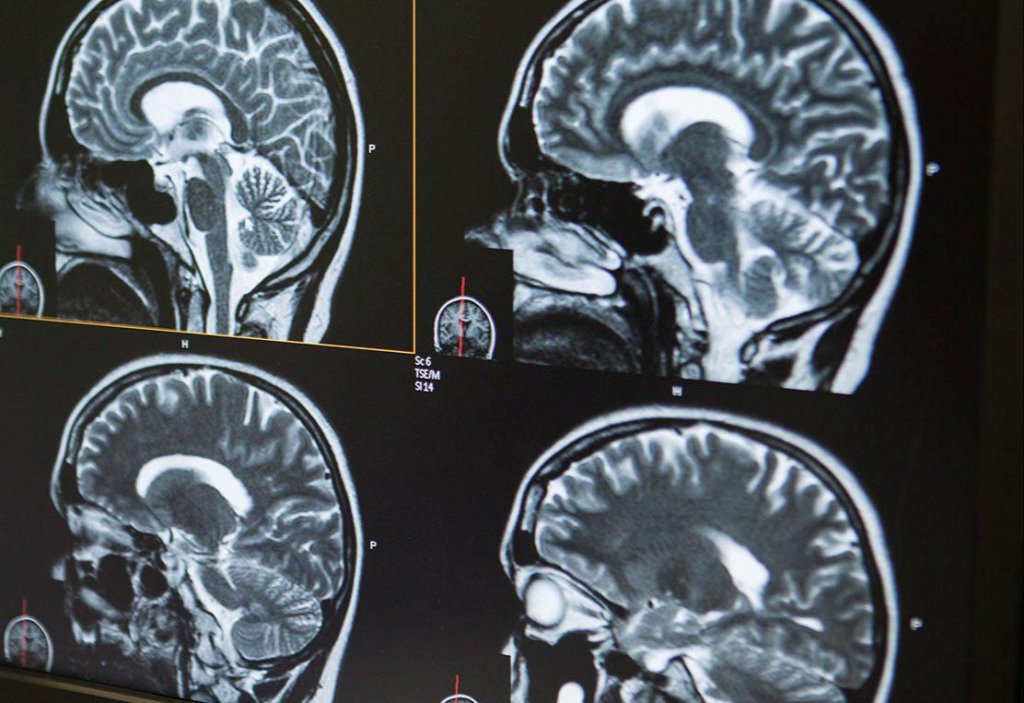

Магнитно-резонансная (МР) трактография мозга

Магнитно-резонансная трактография — это высокотехнологичный метод визуализации белого вещества, позволяющий отследить структуру и направление нервных волокон. Метод основан на диффузионно-тензорной томографии (DTI), разновидности МРТ, при которой измеряется движение молекул воды вдоль аксонов. Результатом становится трехмерная реконструкция проводящих путей, которая помогает оценить их анатомию, непрерывность и возможные повреждения.

В отличие от стандартного МРТ головного мозга, трактография отображает не только строение, но и «связи» внутри мозга, визуализируя информационные пути между его участками.

• Процедура проходит в МРТ-кабинете на аппарате мощностью не менее 1,5 Тесла (в идеале — 3 Тесла). Пациент размещается в аппарате, как при обычном МРТ головного мозга. Исследование занимает 30–45 минут, все это время важно лежать неподвижно.

• Для трактографии используются специальные последовательности, позволяющие зафиксировать направление диффузии молекул воды в ткани мозга. Изображения обрабатываются на отдельной рабочей станции, где врач-радиолог строит карту трактов, оценивает их симметрию, непрерывность и целостность.